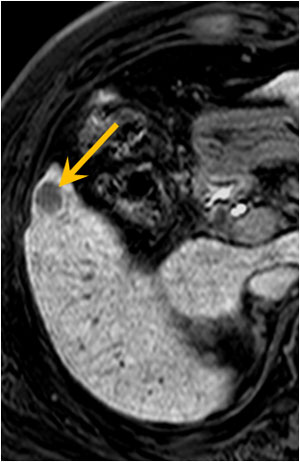

肝細胞がんのプリモビスト造影MRI(脂肪抑制dynamic MRI)

プリモビストは、肝細胞に取り込まれる肝細胞特異性造影剤で、肝細胞機能を反映いたします。

本症例では、少量(5~10 ml)の造影剤で、肝細胞がんが明瞭に描出されております。動脈相では早期濃染しております。腫瘍部は肝細胞機能を持たないため、肝細胞相では造影欠損像として描出されております。

肝細胞がんの検出能は、造影MRIの方が造影CTよりも優れております。